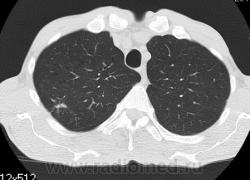

КТ - ОГК.  Ваше мнение коллеги?

На фоне консолидации полость без содержимого. Может быть всё что угодно, что сопровождается деструкцией. Нужны ещё томограммы в лёгочном окне.

Изображения выставлены все. Ваше мнение уважаемые коллеги?

Туберкулёз.

Туберкулёз?